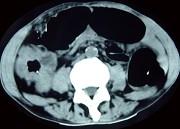

问题 男,70岁,右下腹胀,腹痛,腹泻,影像检查如图,最可能的诊断是 ( )

选项 A.结肠克隆恩病 B.结肠癌 C.结肠套叠 D.结肠结核 E.结肠淋巴瘤

答案 B